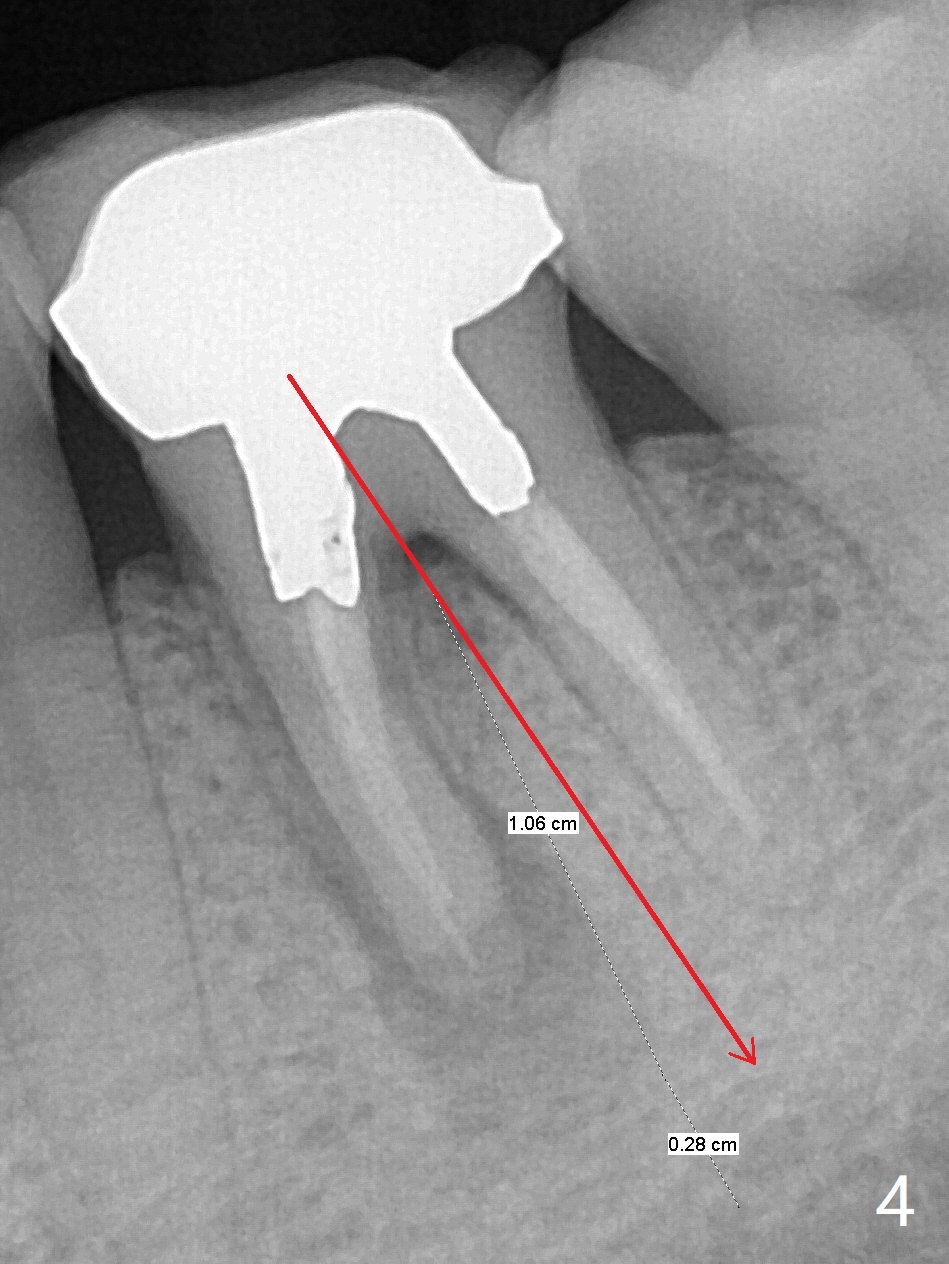

A 53-year-old man has had pain with chewing gums at #19 for 3 years (Fig.1). While a 7x17 mm implant was immediately placed at #30 six years earlier, a 5x17 mm one will be inserted at #19 as lingual as possible to reduce buccal thread exposure (Fig.2). The whole tooth will be extracted before osteotomy in the septum, since the roots in the sockets do not help free hand osteotomy unless the crown breaks off during extraction. Initial depth will be 14 mm. Use Tatum 17 mm drills. Drills are more likely deviated to the mesial socket with large PARL (Fig.1 *). Use visual acuity to correct deviation as early as possible. Pack sticky bone into the mesial bony defect for repair. Take photos of #19 and 30 for buccal recession and fistula if present. It is safe to place a 11 mm long bone level implant (Fig.3,5). It would be ideal to establish initial osteotomy as indicated by the red arrow (Fig.4).